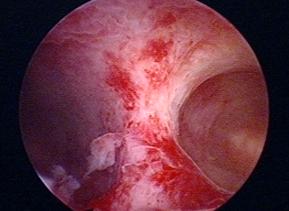

多年前的手术是经腹部切开子宫,把子宫中的这一道隔切除,那术中是血淋淋的,术后恢复时间也较长,还会留下难看的疤痕。而目前,子宫纵隔手术都是通过宫腔镜进行的,宫腔镜是通过阴道和宫颈管这一自然腔道,术后不留任何疤痕,也是妇科最微创的手术之一。